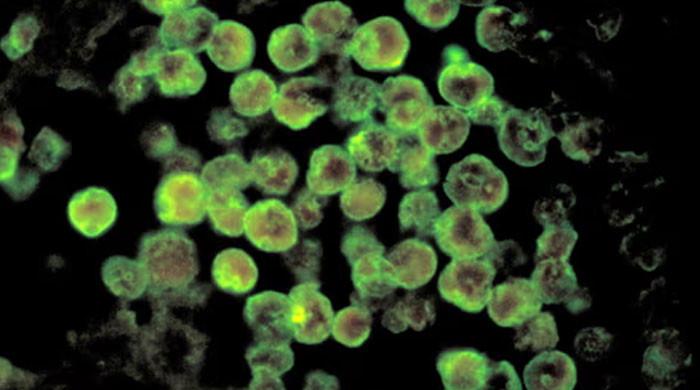

نیگلیریا کیا ہے اور ہم کیا کر سکتے ہیں؟

ڈاکٹروں اور صحت کے ماہرین کا کہنا ہے کہ نیگلیریا عام طور پر دماغ میں داخل ہوتا ہے اور اعصابی نظام پر حملہ کرتا ہے جب متاثرہ پانی ناک کی گہا کے ذریعے نہا رہا ہے ، جب نہانے ، تیراکی یا عدم استحکام کا مظاہرہ کرتا ہے۔

مہلک امیبا گرم پانیوں میں بیکٹیریا پر زندہ رہتا ہے اور اسے صرف مناسب کلورینیشن یا پانی کے ابلتے ہوئے ہی ختم کیا جاسکتا ہے۔

امیبا ، جو گرم ، غیر علاج شدہ پانی میں پروان چڑھتی ہے ، ناک کے ذریعے جسم میں داخل ہوسکتی ہے اور دماغ کے مہلک انفیکشن کا سبب بن سکتی ہے۔